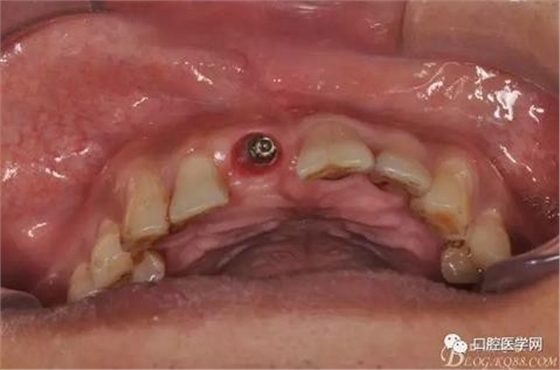

圖7 術(shù)后植入愈合基

圖10 三個(gè)月后袖口形成頜面照